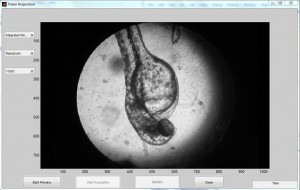

Por su parte, Miguel Ángel realizó un sistema dedicado a la detección y cuantificación automática de la frecuencia cardíaca en la larva del pez cebra: “El conteo manual de los latidos puede ser un proceso muy tedioso, sobre todo porque la larva mide solo 3.5 milímetros y generalmente se trabaja con grupos de 20, 30 o hasta 50 larvas. Una pequeña distracción te puede costar muchas imprecisiones o la necesidad de repetir el conteo una y otra vez”.

Medición de la frecuencia cardiaca de la larva

Medición de la frecuencia cardiaca de la larva

Para evitar esta complicada tarea, Miguel Ángel aplicó un análisis del espectro de frecuencias a la señal de los latidos del corazón, obtenidos a partir de videos de la larva tomados directamente del microscopio, para luego implementar un clasificador que de acuerdo al análisis en el espacio de frecuencias de la señal, determine si la larva está bajo el influjo de un fármaco o no.

“Podemos considerar exitoso este sistema porque nos brinda rapidez y precisión, pues no existen diferencias estadísticamente significativas entre el método presentado y el conteo manual. Además, requiere de una inversión mínima, en contraste con otros equipos que a nivel comercial se venden hasta en 14 mil dólares”, concluyó.